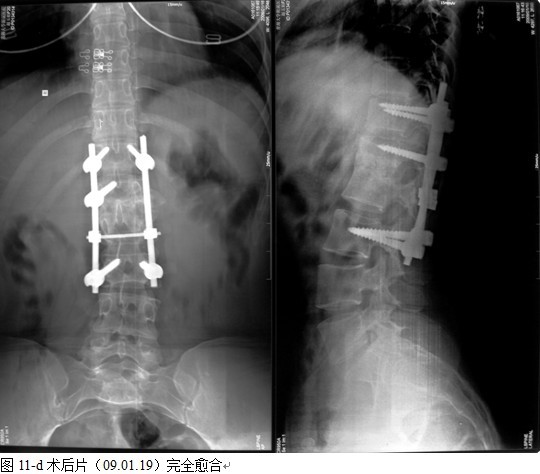

本组手术用时间3~4h , 平均3.5h 。术中出血300~500ml , 平均约350ml 。术后症状完全缓解,无神经功能障碍加重等并发症,1例营养差的老年患者伤口出现窦道,1例因肝功能差,术后未口服抗痨药,伤口出现窦道,经换药后二期愈合,其余病例伤口均一期愈合。马尾神经受损的患者术后基本恢复正常。术后一周后凸角平均 5.4°后凸畸形平均矫正90%以上, 最终后凸角平均8.3°,后凸角度平均丢失4.2°。随访3个月有87%(40/46)有骨痂形成,6个月91.3%(42/46)明显骨性愈合(见图),其余4例9-12个月内愈合,随访时间3-32个月,平均11个月,46例患者中2例在术后2个月和3个月时背部形成脓肿,换药后治愈。2例出院1月后并发结核性脑膜炎,治疗后好转。1例因椎弓根钉偏外,刺激神经根,5个月后从侧方脱出,疼痛加重,因前后路植骨完全愈合,取出后症状完全缓解。

中国学者金大地[22]等采用一期前路病灶清除植骨前路钢板固定治疗腰椎结核,平均18°的后凸畸形得以矫正,Mukhtar[23] AM等采用前路病灶清除植骨分期或同期后路固定治疗腰椎结核22例,术后后凸畸形矫正度数平均为27°。从我们的随访结果看,术后后凸畸形平均矫正度数为26.9°,后凸畸形平均矫正90%以上, 6个月-49个月后随访,后凸角度平均丢失4.2°。本术式也适用于结核所引起的弹性差的后凸畸形,对于病灶纤维化或骨化的非弹性后凸畸形,后路固定后,先行前路病灶、纤维化或骨化切除、松解,逐步刮除病灶、逐步撑开,达到畸形矫正和植骨的目的。